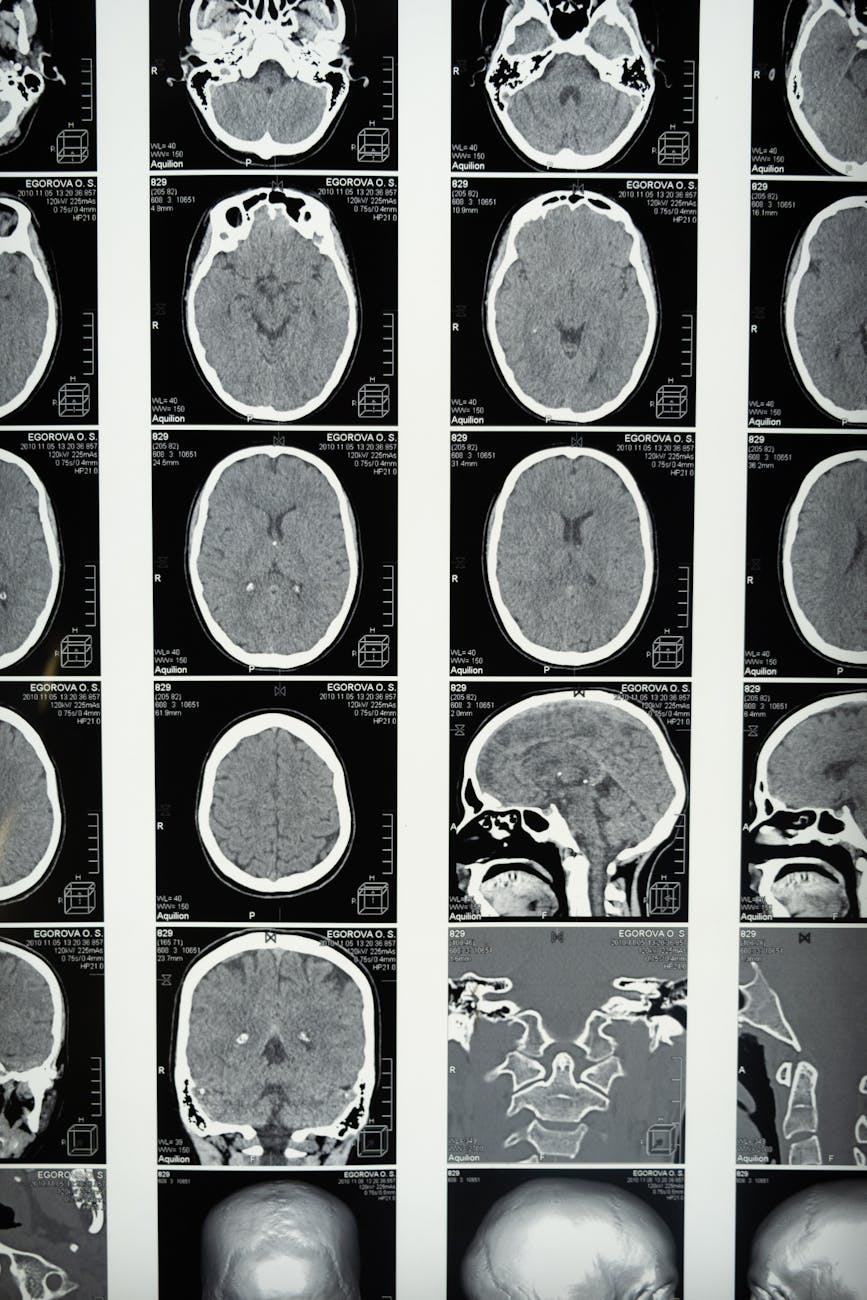

medical imaging of the brain

Photo by cottonbro studio on Pexels.com

In de middag werd het plan van aanpak besproken. Diverse bloedafnames, echoยดs, een aantal ECGยดs, een lumbaalpuctie, een uitgebreide MRI van de hersenen en ruggengraat en gesprekken met een team om te bepalen welke hulp er nodig zou zijn om het leven makkelijker te maken.